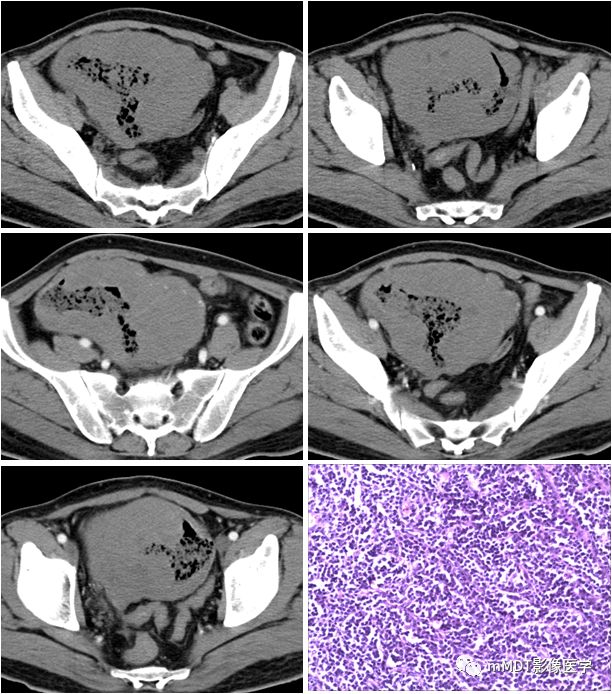

病例7:女,39岁,腹痛2月余,淋巴瘤(未分型)

qw12.jpg

CT表现:回肠末端肿块,密度均匀,轻度均匀强化,合并肠套叠,肠系膜及腹膜后多发肿大淋巴结,淋巴结信号均匀,轻度强化。

病理:回肠隆起型淋巴瘤,肿块3.5×2.5×1.5cm,侵及全层。肿块外膜面检淋巴结13枚,见其中5枚为淋巴瘤。